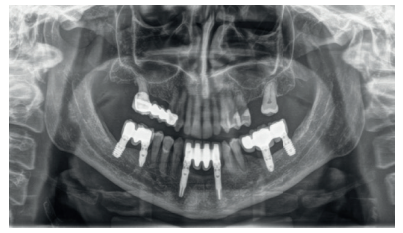

Finally, the stability of both treatments can be seen in the final X-ray at 8 years of age, where both are stable without bone loss (Figure 13).